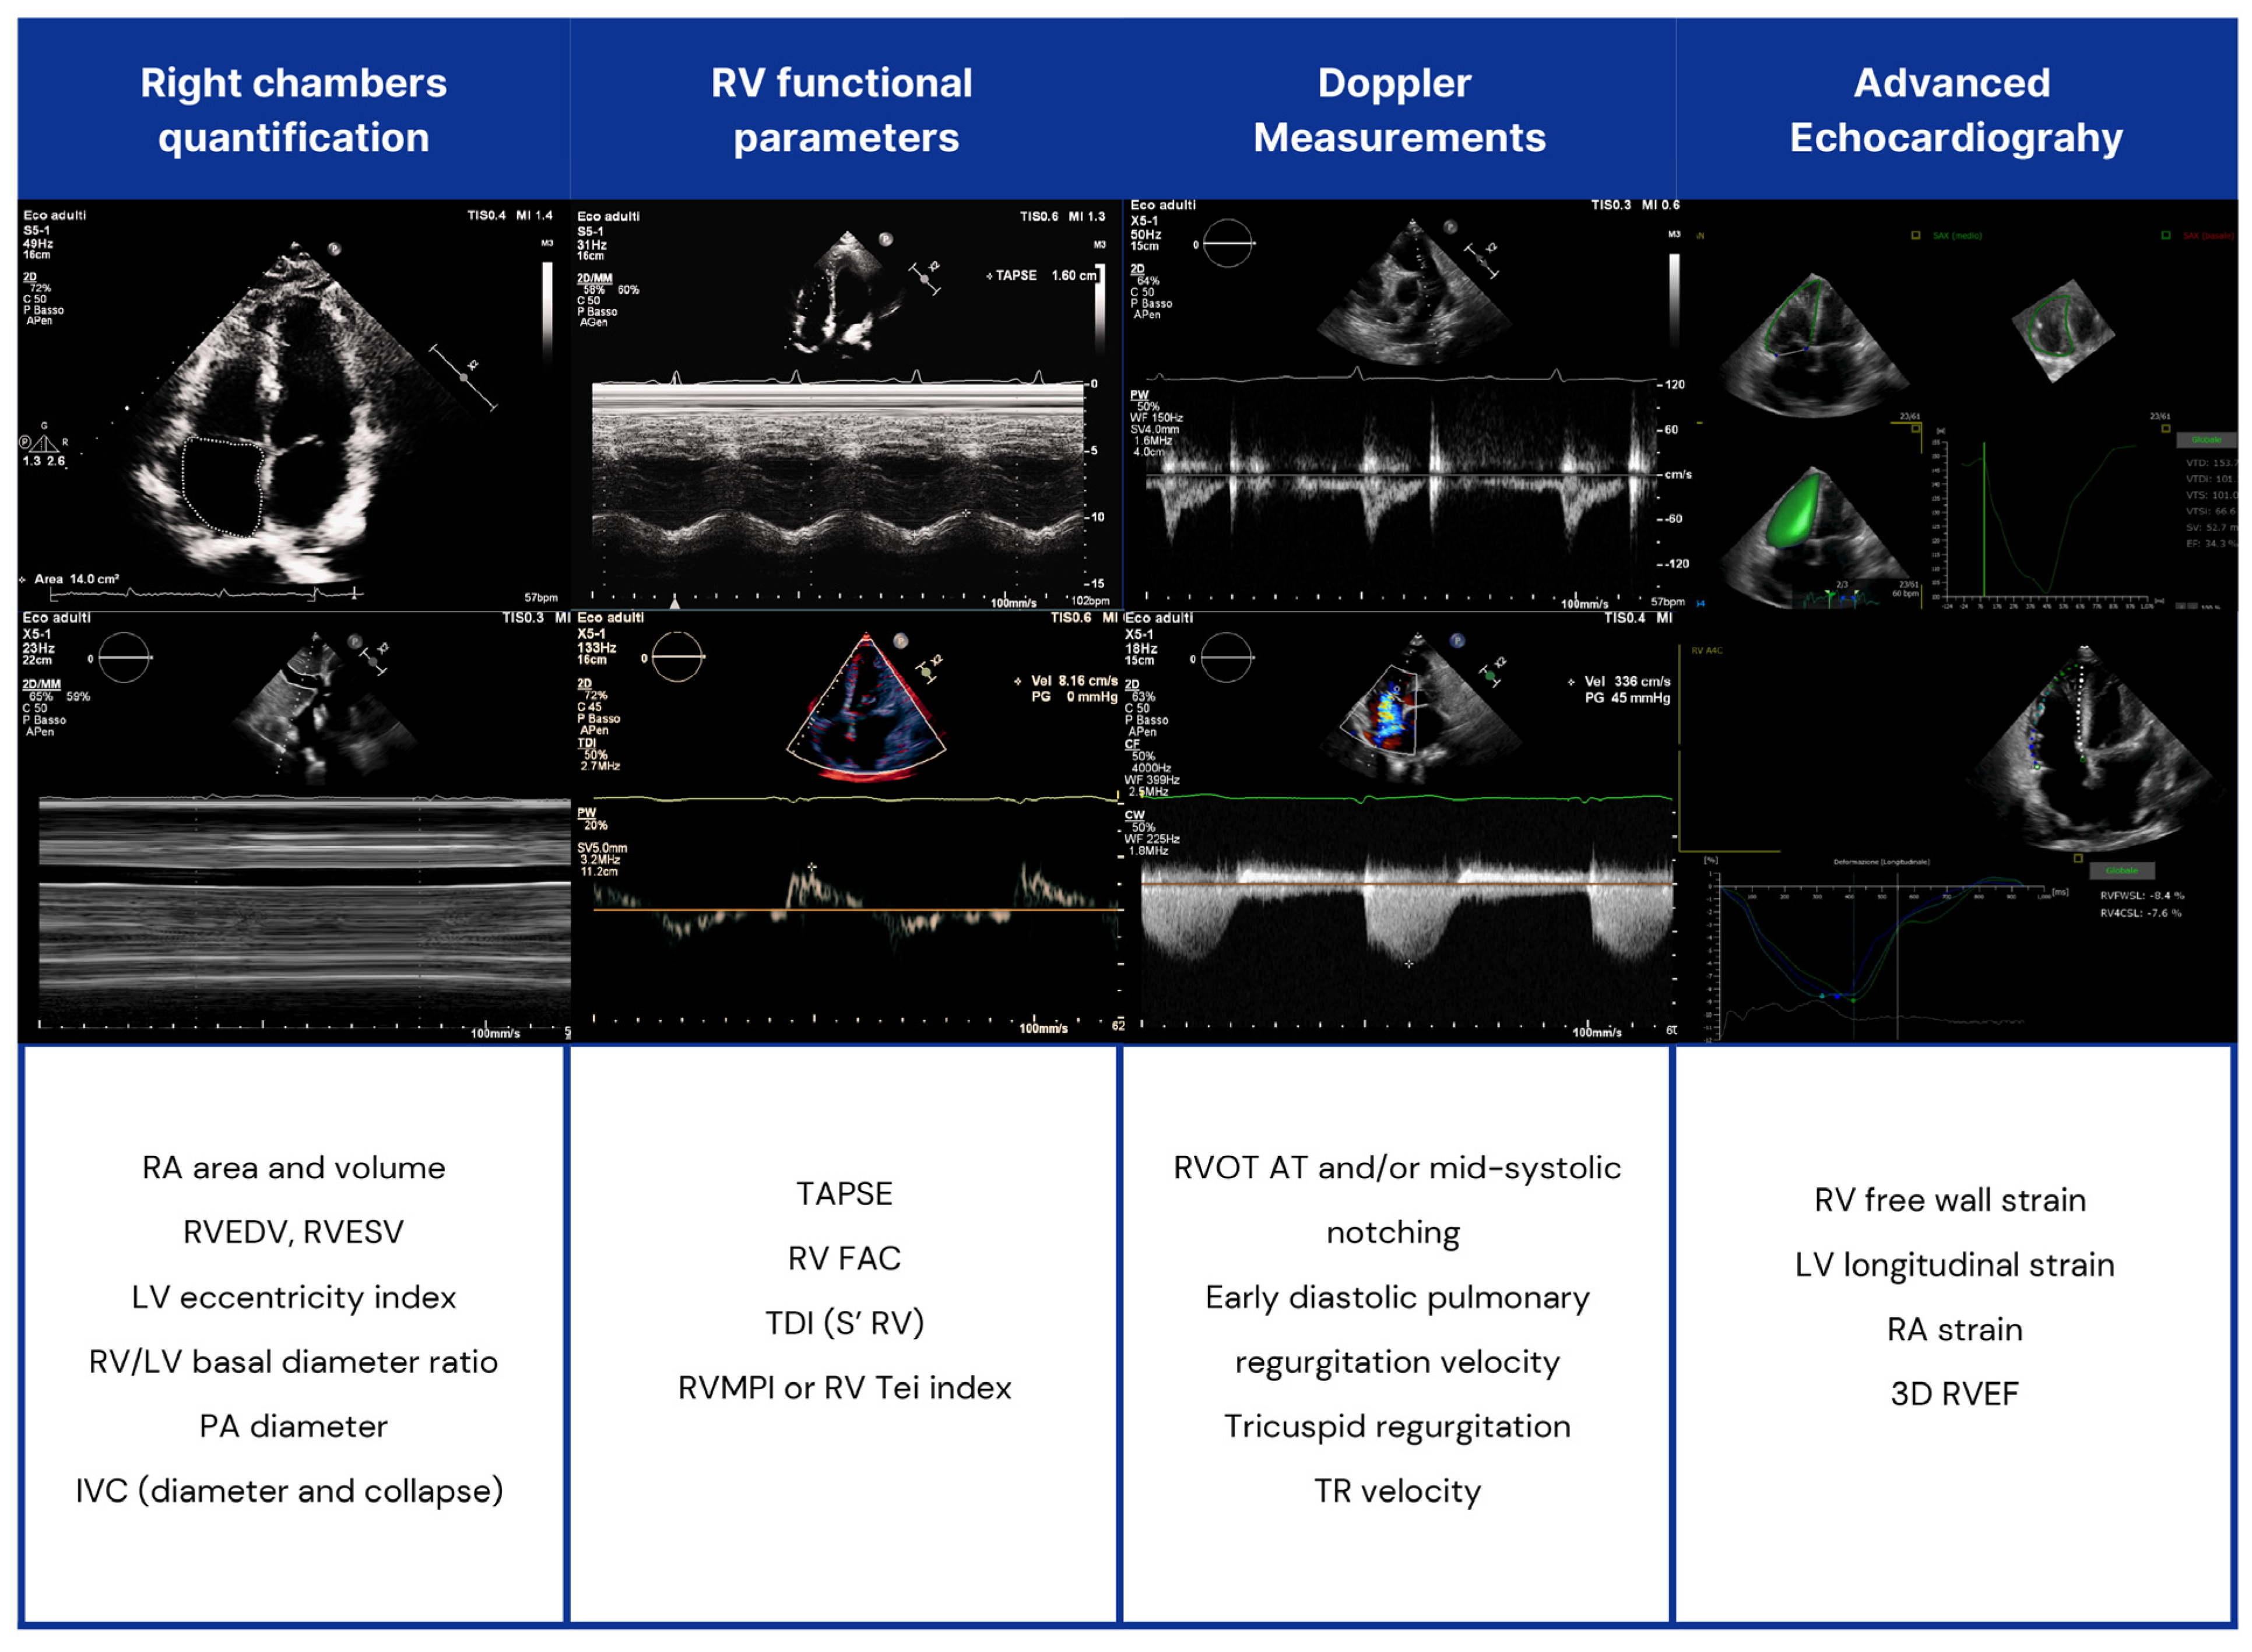

2.1. Two-Dimensional Echocardiographic and Doppler Measurements

| Two-dimensional echocardiography |

|

| Three-dimensional echocardiography |